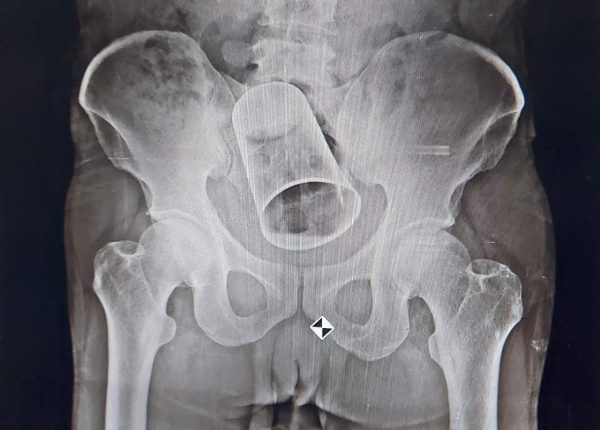

The doctors were able to determine that the glass had been inserted inside the bowel after an X-Ray was performed. The steel glass was then extracted from Krushna's gut through surgery on August 19 at the MKCG Hospital.